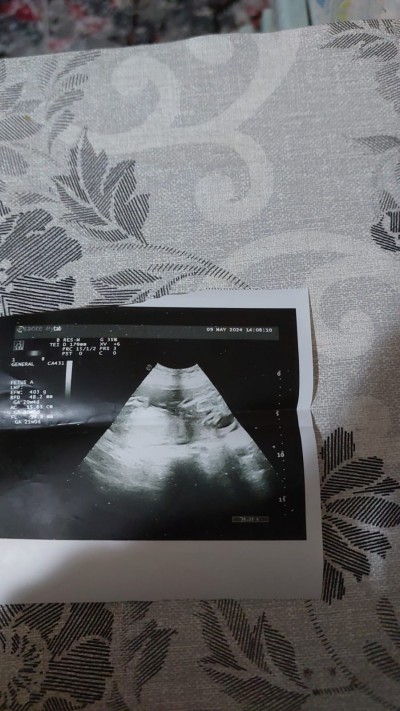

Kızlar sorum 21 haftalik hamileyim önce erkek dediler bu gün kiz dedi bu haftada normal mi

image

Benim başıma ilk defa geldi resim de koydum ama kimse yok